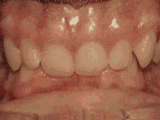

前牙移位,因为有牙齿缺失,导致相邻牙齿开始没有秩序的左右移动,经过矫正后是变成这样的~